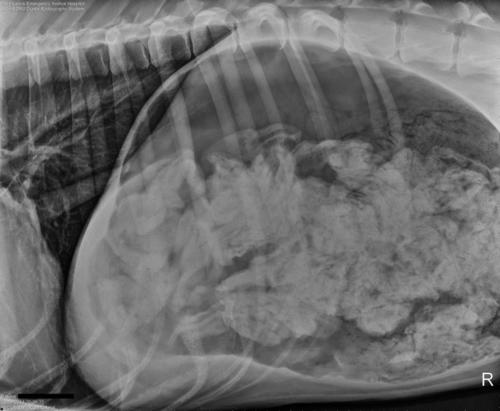

Los dueños del gran danés, de tres años de edad, llevaron al veterinario al canino que empezó a vomitar y quejarse por el dolor en su estómago. Esta es la radiografía:

El perro tuvo que ser intervenido quirúrgicamente y los 43 calcetines y medio quedaron para ser recordados.